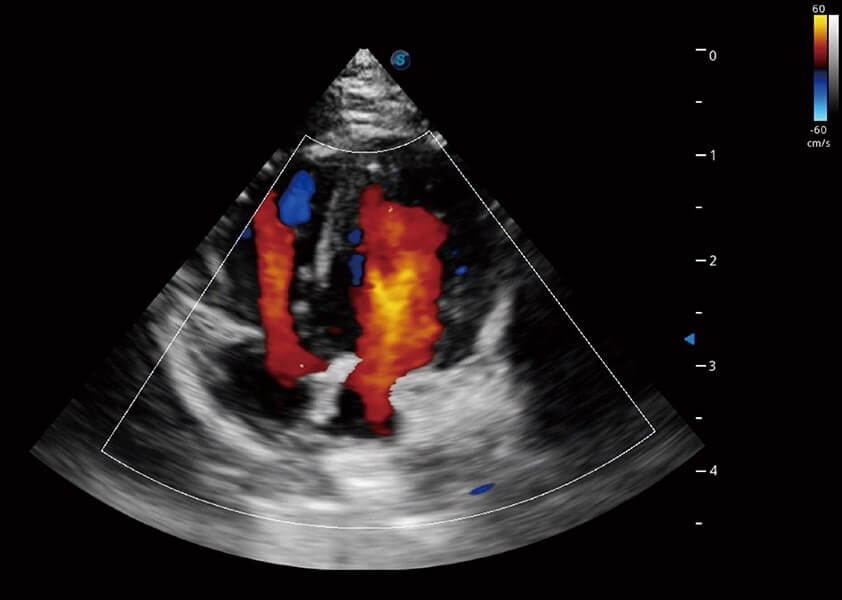

ProPet 60 作为一款高端台式动物超声设备,为动物医生的日常诊断提供了一系列贴合动物临床需求、解决临床实际问题的高级成像功能。凭借全系列高清探头,满足医生对腹部、心脏、生殖、浅表、肌骨等成像的所有需求,切实帮助您提升检查效率,提高诊断信心。

动物是人类最亲密的朋友和最值得信赖的伙伴。玖鼎集团也一直致力于探索动物专用的超声影像解决方案。 全新推出的ProPet系列,是玖鼎集团在动物超声影像智能化、专业化、精准化的一次跨越式革新。动物不能用言语来表述自己的不适,通过超声影像,ProPet系列搭建了动物医生与不同物种沟通的“桥梁”,为动物医生注入了“治愈之力”。